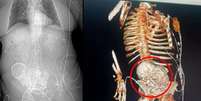

Mulheres relatam gravidezes inesperadas ao tomarem medicamentos para perda de peso, como Ozempic e Mounjaro, conforme compartilhado em redes sociais. Esses relatos abrangem desde usuárias de anticoncepcionais até aquelas com histórico de baixa fertilidade.

Os medicamentos podem aumentar as chances de gravidez em mulheres com distúrbios metabólicos ligados à fertilidade

Segundo o Metrópoles, o obstetra Nathan Ichikawa Ceschin destaca que mulheres com Índice de Massa Corporal (IMC) acima de 35 têm maior propensão a abortos espontâneos. Ao perderem peso, reduzem esse risco. Este fenômeno levanta questões sobre a influência desses medicamentos na fertilidade e destaca a importância de uma orientação médica adequada ao utilizá-los.

O ginecologista Luís Otávio Manes, de Brasília, explica ao Metrópoles que tais medicamentos podem aumentar as chances de gravidez em mulheres com distúrbios metabólicos, como diabetes e obesidade. Isso acontece, pois esses problemas afetam a produção hormonal ligada à fertilidade. "Mulheres que não ovulavam todos os meses passam a ovular de maneira regular e, obviamente, aumentam a probabilidade de engravidar. Além dessas situações, a medicação não ajuda em absolutamente nada na taxa de gravidez e nem na fertilidade", considera Manes.

"O fato de emagrecer, perder peso e melhorar a saúde impacta na fertilidade, ou seja, os "bebês de Ozempic" podem ser um efeito indireto da medicação", considera o médico, que é integrante da Associação Brasileira de Reprodução Assistida (SBRA). "Uma vez que se consegue eliminar o peso e diminuir o IMC, isso melhora as condições de ciclo menstrual", completa Ceschin.